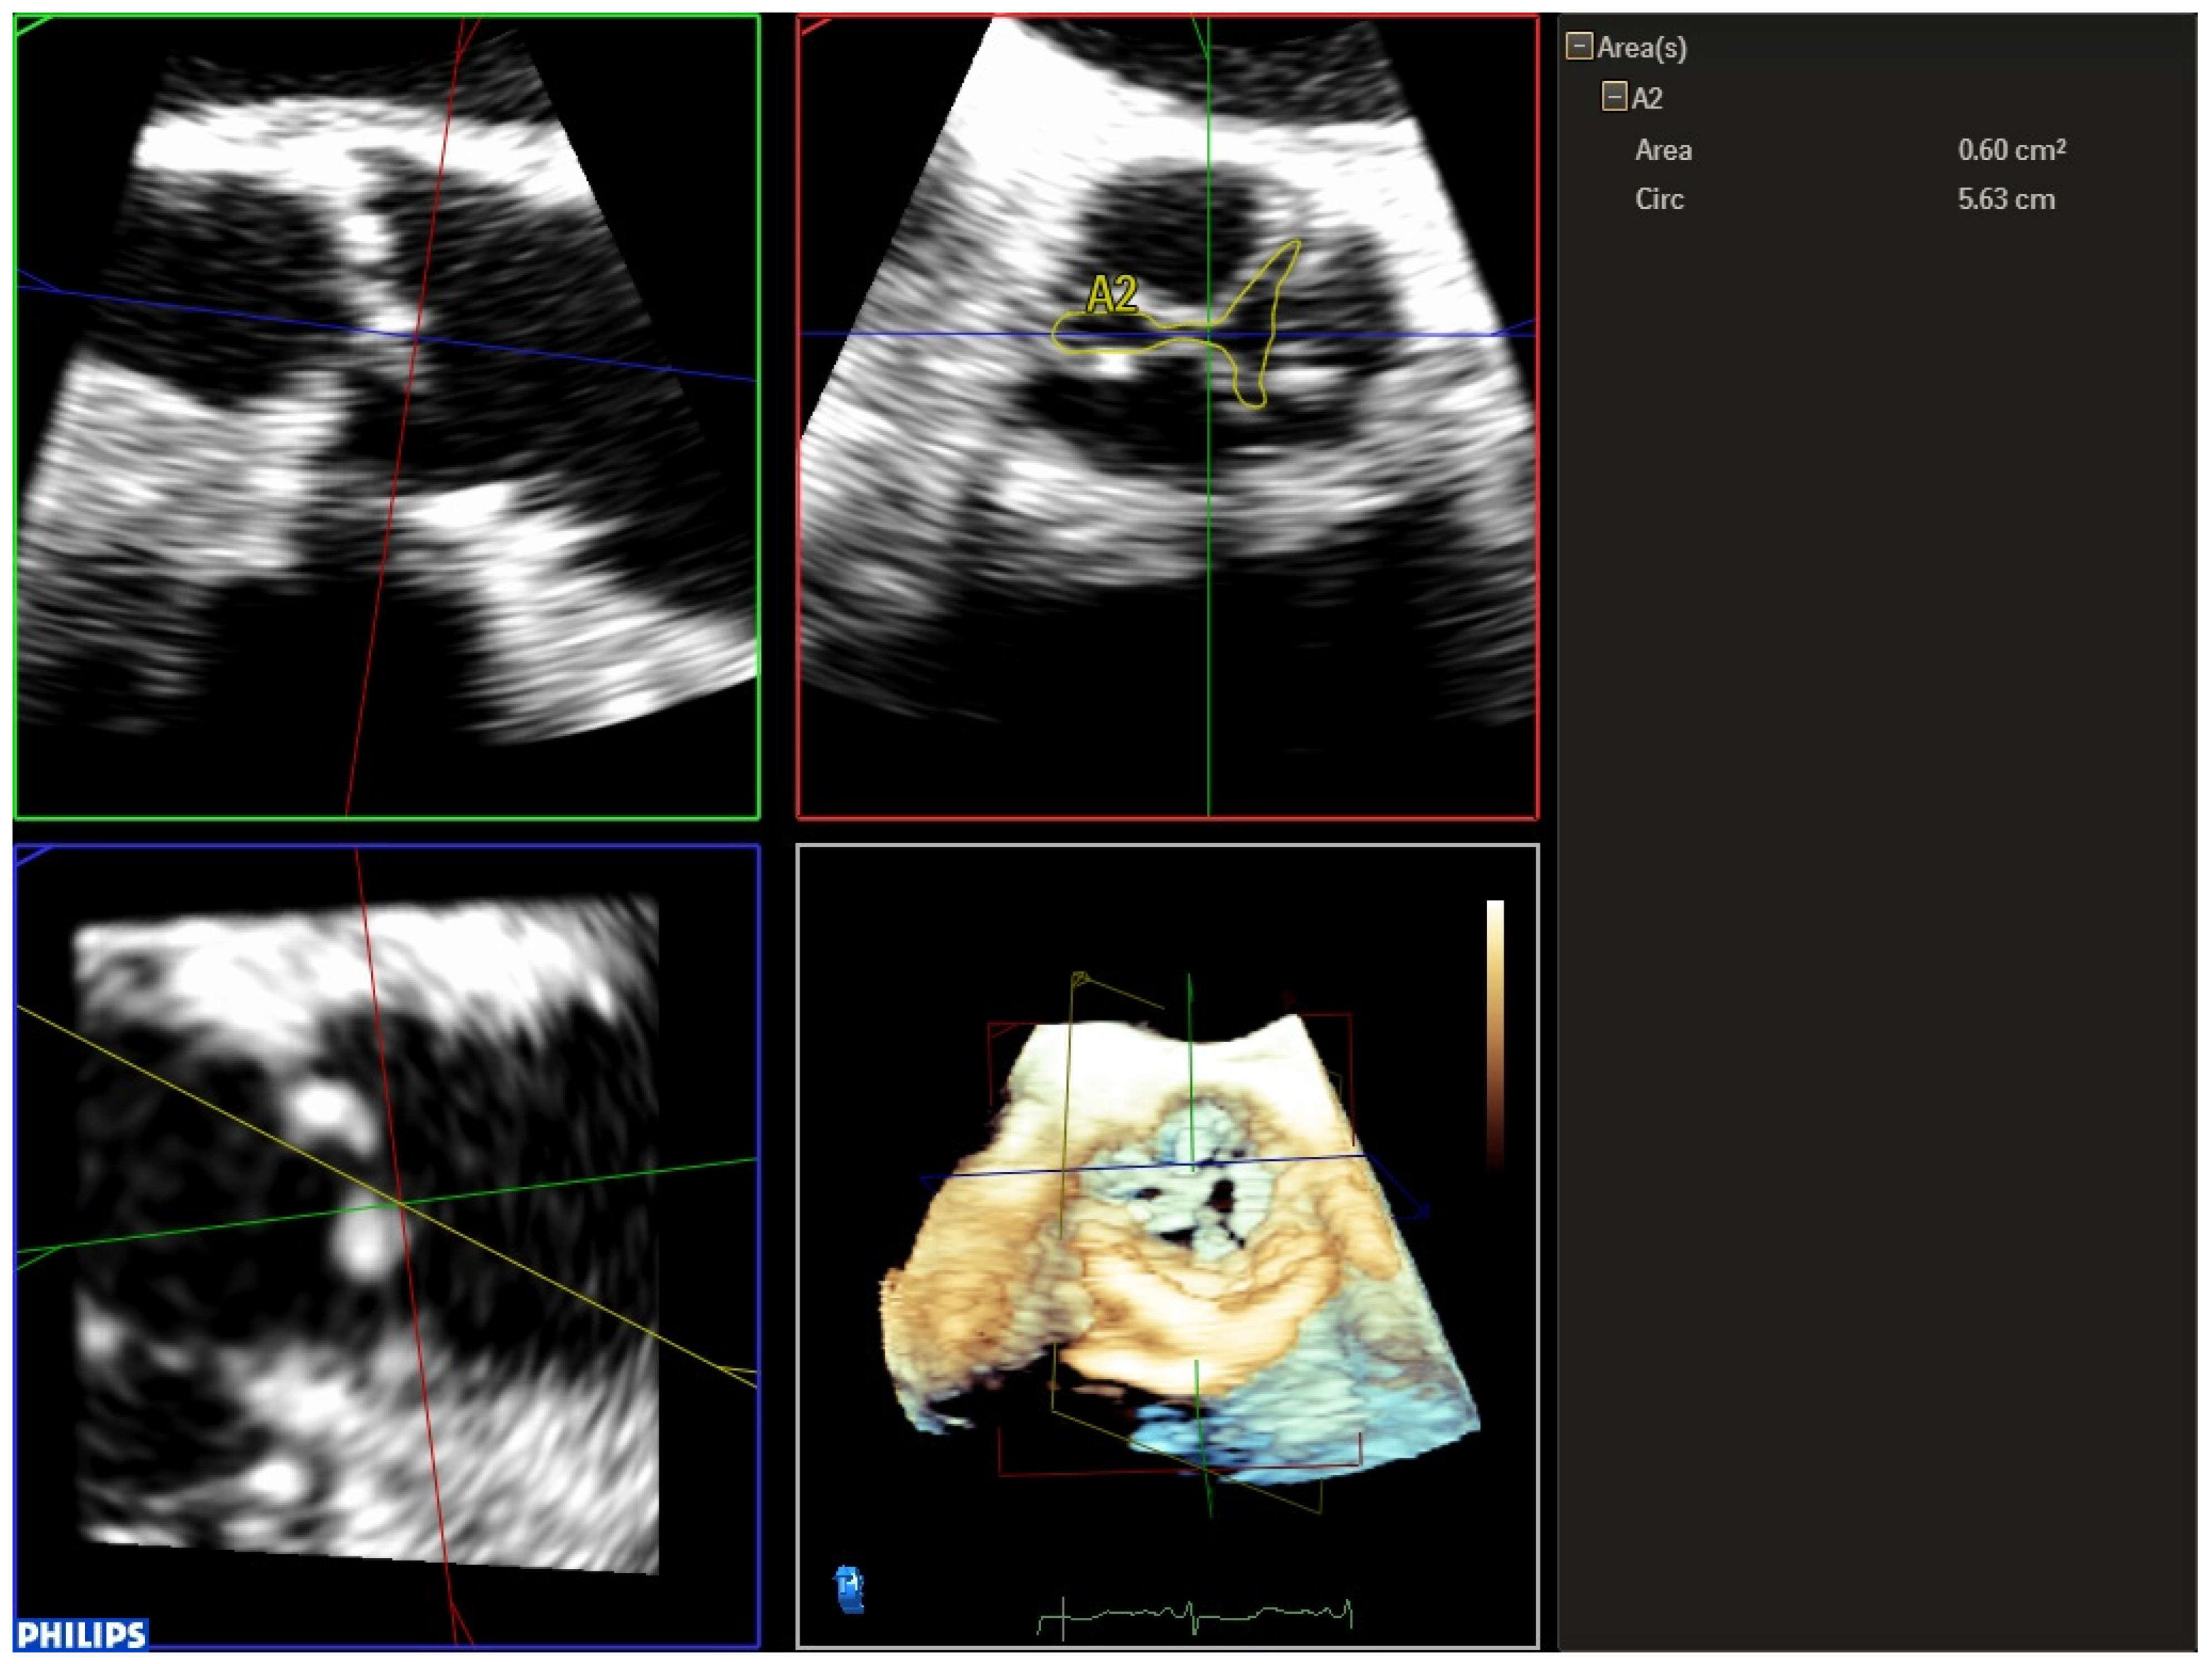

Three-dimensional TEE makes it possible to quantify aortic regurgitation more precisely. Visualization of two orthogonal planes with the biplanar color method localizes the jet and evaluates the mechanism and severity of aortic regurgitation more accurately than 2D-TEE (Figure 6 and Video S17). Planimetry of the vena contracta area by 3D-TEE facilitates a better classification of moderate regurgitation [18]. Another possible complication of the procedure is embolization of the prosthesis, which is a rare and serious complication that must be diagnosed quickly (Video S18). Sometimes there is a displacement of the prosthesis towards the LVOT, which can cause mitral regurgitation due to restriction of the anterior mitral leaflet. Displacement towards the aorta can cause occlusion of the coronary ostia and, as a consequence, ventricular dysfunction. The presence of QRS widening or hemodynamic deterioration with abnormalities in segmental contractility after expansion of the prosthesis should alert physicians to possible compromise due to coronary artery obstruction. In one study, 70% of patients with coronary obstruction had a left main coronary artery height < 12 mm and a maximum aortic root diameter < 30 mm. It is also important to evaluate the aortic root, since it could have increased in thickness due to an intramural aortic hematoma (Video S19) or an aortic dissection. The sudden appearance of pericardial effusion (Video S20) should alert physicians to possible ventricular perforation or rupture of the aortic annulus.

Figure 6.

Evaluation of post-TAVR perivalvular aortic regurgitation using 3D-TEE in biplanar mode (X-plane). In the short axis, it is observed that regurgitation covers more than 30% of the circumference, which corresponds to severe regurgitation.